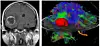

Biletet til venstre viser korleis hjernesvulsten blir oppdaga med avanserte bilete. Til høgre kan ein sjå ein 3D rekonstruksjon over korleis hjernesvulsten i raudt ligg i høve til dei andre strukturane i hjernen (nervefibrar med meir). Foto: Terje Sundstrøm ved Nevrokirurgisk avd. Haukeland Universitetssjukehus